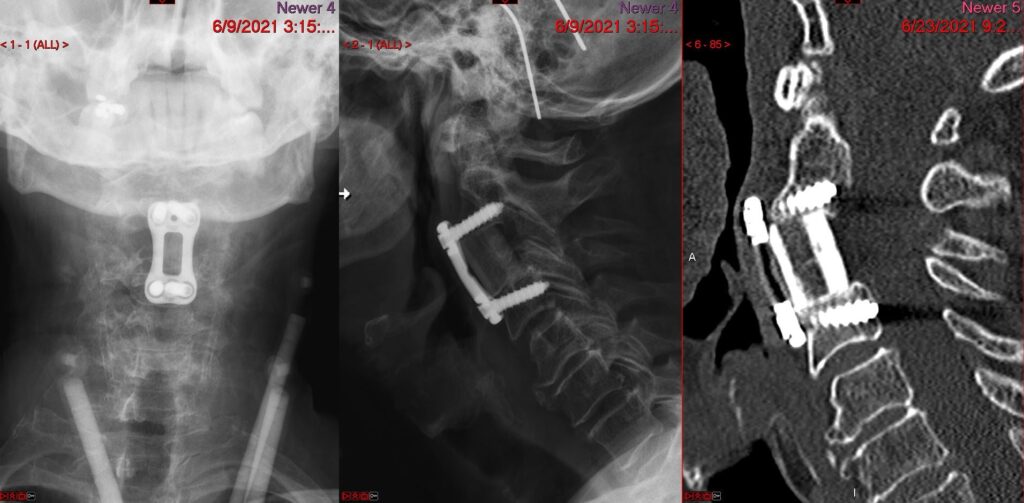

ACCF Preop 1024x507

ACCF Postop 1024x503

Anterior Cervical Corpectomy and Fusion

c5 corpectomy ct

c5 corpectomy

anterior cervical c5 corpectomy and fusion